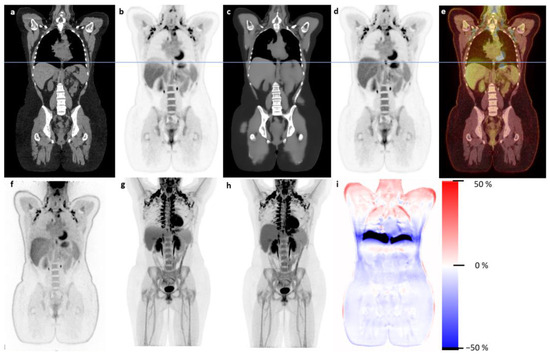

3.1. Qualitative Evaluation

3.2. Quantitative Evaluation